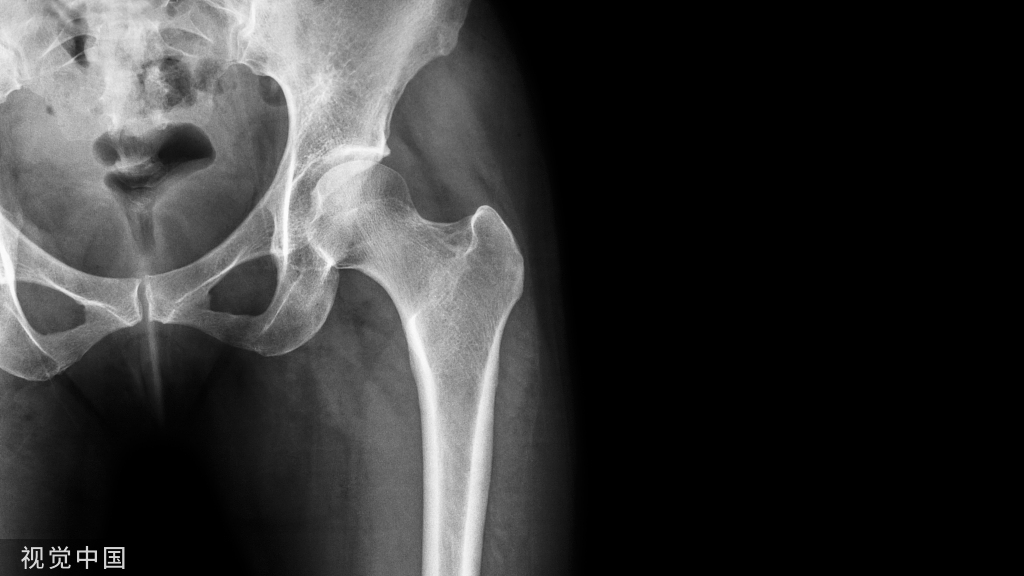

髋臼骨折在骨科领域是一种严重的创伤,其发病率较低。随着我国步入工业社会,机动车数量的增加,髋臼骨折的发生率也随着逐年增加;目前我国正步入老年社会,老年人及骨质酥松患者的髋臼骨折的报导也越来越多。这些将使骨科医生对髋臼骨折投入更多的关注。然而,髋臼的解剖位置深在,且骨性结构极不规则,加上发生骨折时往往由高能量暴力所致,因此对骨科医生来说,髋臼骨折的治疗仍然是一项重大的挑战。髋臼骨折的治疗由最初的保守治疗到现如今的切开复位内固定,甚至行全髋关节置换治疗,其过程经过了长期的探索。